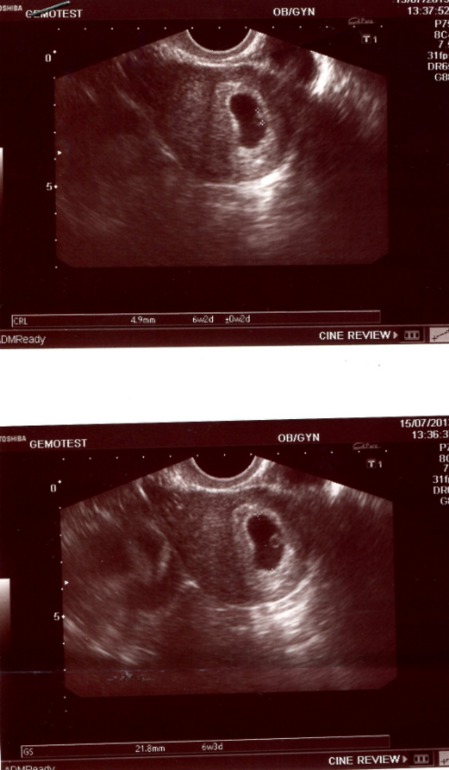

Вчера увидела свою горошинку)))

по УЗИ поставили 6 недель и 3 дня, сердечко бьется, все хорошо.